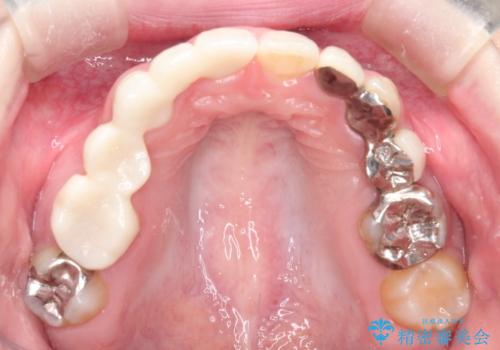

- 保険治療で装着されたかぶせ物と詰め物を変更したいとのことで来院されました。

自然なオールセラミックへ変更することとなりました。

金属を使わないセラミックへ変更することで、自然な見た目になるとともに、ぴったりとした精度の高いかぶせ物を装着することができました。